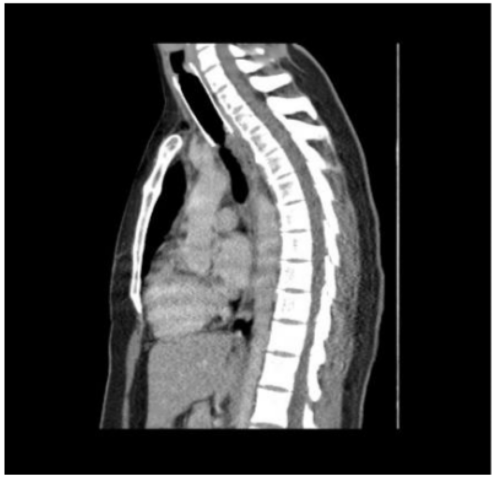

Subsequently she underwent a contrast enhanced CT scan of neck and thorax which showed

• a tracheal stent with proximal end at C6 vertebra and distal tip about 3.6 cm proximal to carina

• heterogenous soft tissue lesion with subtle enhancement in posterior aspect of trachea at D3 vertebral level with intra-tracheal extension causing luminal narrowing suspicious for malignancy

• soft tissue thickening with enhancement at proximal aspect of stent at C6 vertebral level around 1.7cm distal to true vocal cord causing tracheal narrowing with narrowest diameter of 6mm? granulation tissue/? malignancy

• sub-centimetric para-tracheal and pre-carinal lymph nodes

• varying sized nodules scattered in both lungs suggestive of metastasis

Image 2: Contrast enhanced CT scan of neck and thorax, sagittal section showing the tracheal stent